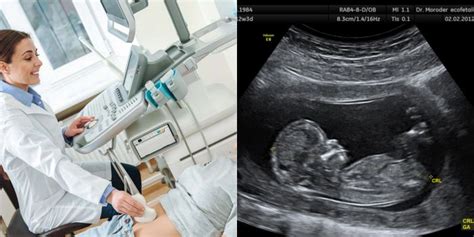

Vaisiaus širdies ritmui stebėti naudojami įvairūs metodai, kurie gali būti taikomi tiek rutininio prenatalinio patikrinimo metu, tiek esant specifinėms indikacijoms. Kiekvienas metodas turi savo privalumų ir yra tinkamas tam tikroms situacijoms.

Tai vienas seniausių ir paprasčiausių vaisiaus širdies ritmo stebėjimo metodų. Jis apima vaisiaus širdies plakimo klausymą naudojant delninį Doplerio prietaisą arba fetoskopą.

- Procedūra: Įprasto prenatalinio vizito metu sveikatos priežiūros paslaugų teikėjas naudos Doplerio prietaisą arba fetoskopą, kad klausytųsi kūdikio širdies plakimo. Šis metodas yra neinvazinis ir neskausmingas.

Šis metodas, dar žinomas kaip kardiotokografija (KTG), yra plačiau naudojamas, ypač gimdymo metu, ir suteikia detalesnę informaciją apie vaisiaus būklę.

- Procedūra: Nuolatiniam stebėjimui teikėjas uždeda du jutiklius ant motinos pilvo. Vienas jutiklis matuoja kūdikio širdies ritmą, o kitas stebi gimdos susitraukimus. Šie jutikliai yra tvirtinami elastine juosta.